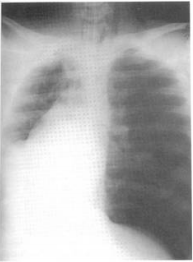

65.一青少年因車禍送至急診,插管後,心搏每分鐘160次、呼吸24次、血壓95/60毫米汞柱, FiO

2

100%時,其血液氧氣飽和度為100%,血比容29%。聽診時左側呼吸音較小聲,胸部X 光如圖,請問立即措施為: (A)立刻放置左側胸管引流 (B)立即輸血紅血球濃縮液(Packed RBC) (C)心包膜切開術 (D)照會外科